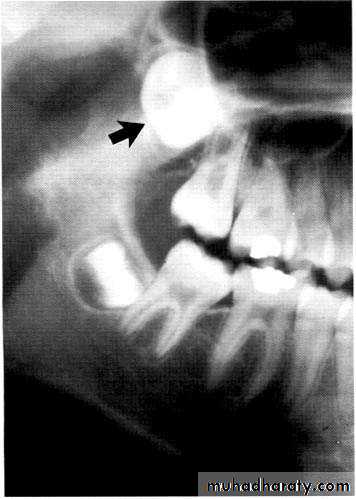

Paramolar blocking the eruption of 3rd molar.

Many supernumerary teeth never erupt, but they may delay eruption of nearby teeth or cause other dental problems.

If they erupt, they can cause malalignment of the normal dentition.

They may cause root resorption or interfere with the normal eruption sequence.

Follicles of unerupted supernumerary teeth occasionally develop

into dentigerous cysts.